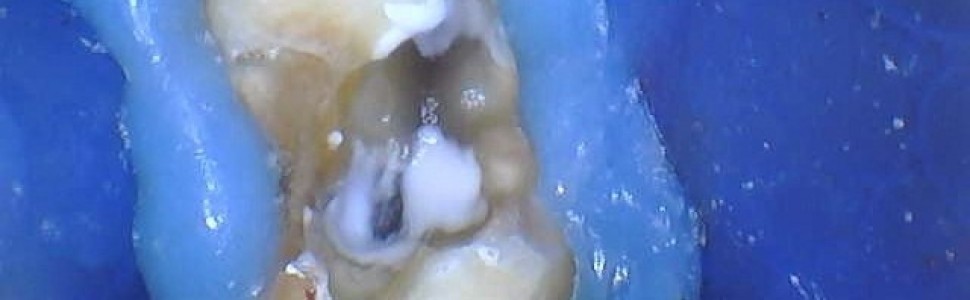

Ewolucja materiałów bioaktywnych – ich zastosowanie od endodoncji po protetykę

W artykule opisano dwa przypadki leczenia endodontycznego, w których zostały użyte materiały bioaktywne, począwszy od zastosowania ich w endodoncji i kontrolę przebiegu gojenia zmian okołowierzchołkowych, poprzez odbudowę rdzenia zęba, kończąc na cementowaniu korony.

The article describes two cases of endodontic treatment in which bioactive materials were used, starting from their use in endodontics and monitoring the healing process of periapical lesions, through the reconstruction of the tooth core, ending with cementation of the crown.